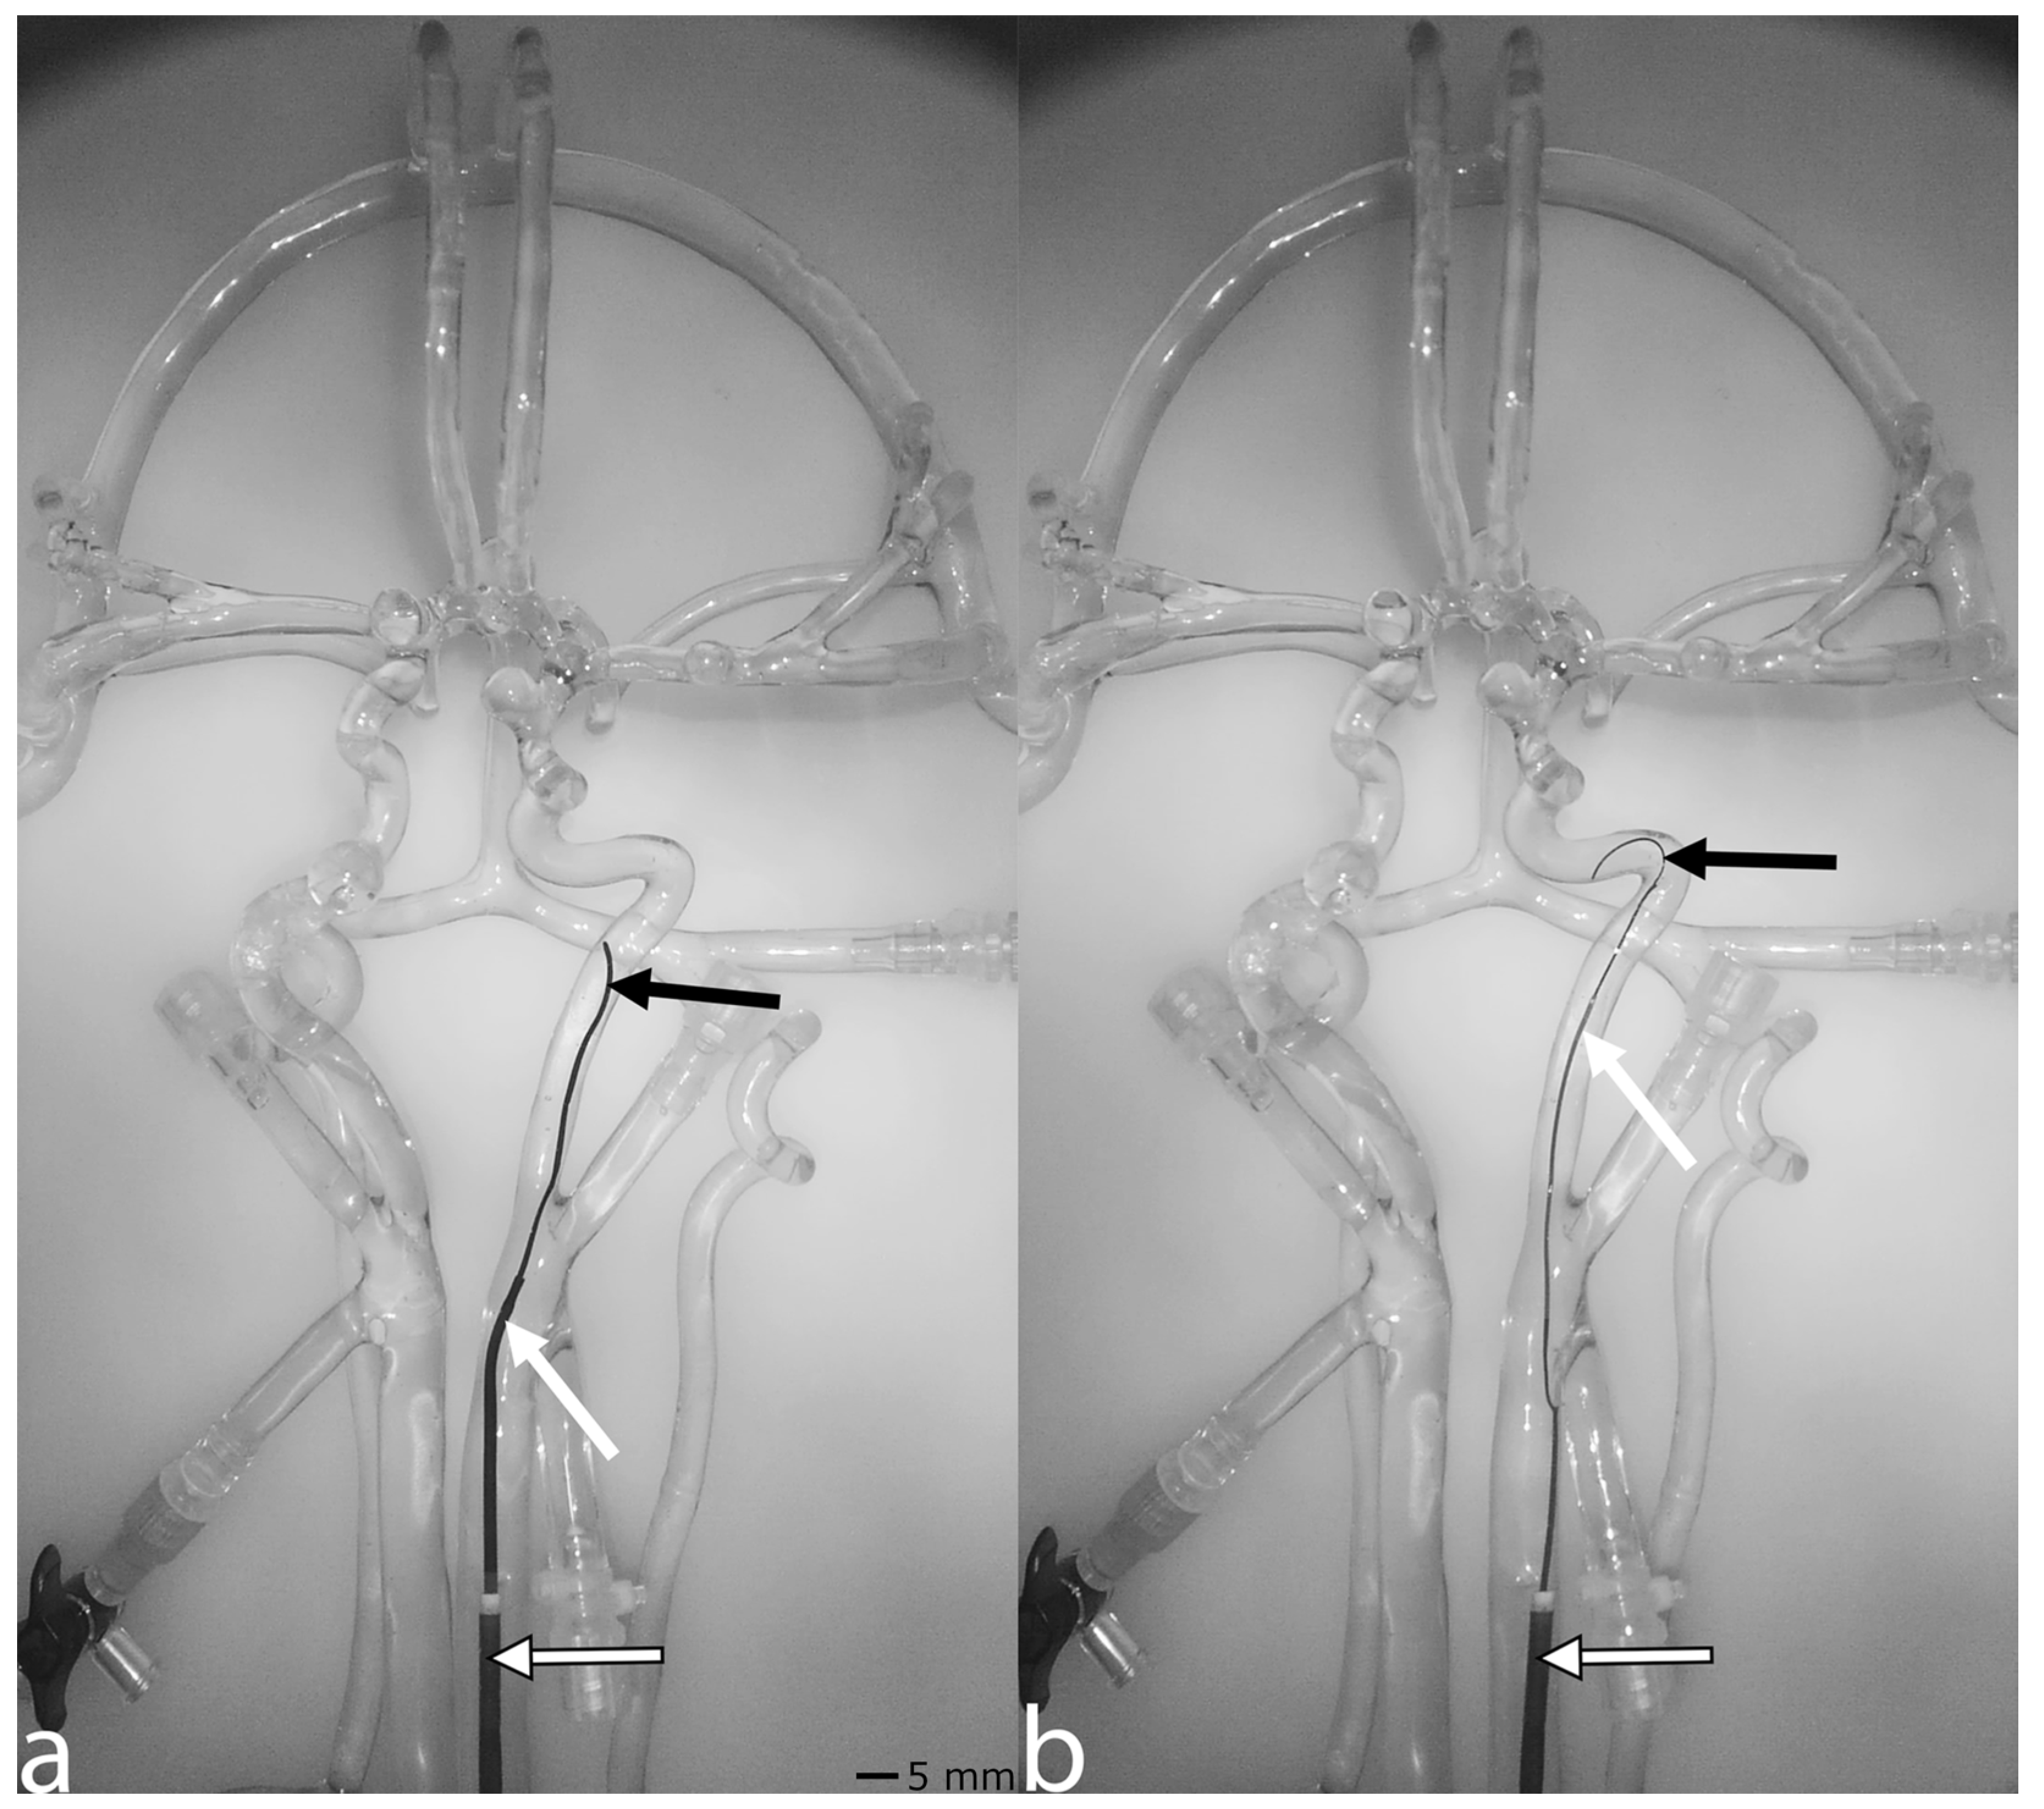

The vascular silicone simulator (Neuro Testing Model Plus, United Biologics, Santa Ana, CA, USA) (Figure 1a) used in combination with the AngioSim is made of soft transparent silicone, enabling the direct visualization of endovascular devices. The silicone model includes the aorta, the supraaortic branches, the Circle of Willis, and the proximal segments of the anterior, middle, and posterior cerebral artery. The vascular silicone simulator is filled with distilled water at room temperature, and soap is added to reduce friction. To simulate blood flow, the inlet of the vascular silicone simulator at the aortic arch is connected to a pulsatile pump (Figure 1i), which is connected to a water reservoir (Figure 1j). When not used with AngioSim, the simulator is typically paired with a camera (Figure 1b), with the video feed displayed on a screen (Figure 1c) in front of the physician.

The AngioSim consists of two main compartments: the traditional vascular silicone simulator (as described above) with components for flow control and basic visualization (Figure 1a–c,i,j), and the platform that enables the simulation of angiographic procedures (Figure 1d–h,k,l).

To perform a DSA or RM, a ready-made red dye solution (Supreme Blood Internal, Kryolan, Berlin, Germany) is used as a contrast agent substitute. To prevent contamination of the entire water volume when the contrast agent substitute is injected into the system, the outlet of the vascular silicone simulator located at the cranial vessels is connected to a 6V solenoid 2-position 3-way fluid valve (Figure 1k), which can redirect the fluid flow from the water reservoir to a wastewater reservoir (Figure 1l). This solenoid valve is controlled by a relay (KF-301 5V 1-relay module, AZ-Delivery, Deggendorf, Germany) (Figure 1g), powered by an external 9V battery. The valve is operated by the AngioSim software v1.0 on a Windows notebook (Figure 1j) via a USB-to-GPIO adapter (Adafruit MCP2221A Breakout—General Purpose USB to GPIO ADC I2C, Adafruit, New York, NY, USA) (Figure 1g).

For image acquisition, a document camera (Epson ELPDC21 Document Camera, Epson, Suwa, Japan) (Figure 1b) is connected to the notebook via USB. The edited visual input is displayed on a 55-inch screen (PH55F-P, Samsung, Seoul, Republic of Korea) (Figure 1c) via HDMI. Two pedals of a PC-compatible programmable three-pedal footswitch (PCsensor USB Programmable 3-Pedal Foot Switch, PCsensor, Shenzhen, China) (Figure 1f) are used to control the X-ray and cine loop functions. If the cine pedal is pressed, the solenoid valve redirects the liquid flow into the wastewater reservoir. The effect of the pedal sustains for additional 10 s after it is released to prevent contrast agent from entering the main compartment. A numeric keypad (LogiLink ID0120, LogiLink, Schalksmühle, Germany) (Figure 1e) is used to control the different modules of the simulator. The total cost of the AngioSim extension amounted to EUR 68.12, which covered the newly purchased components. A detailed price list of these materials is available at https://zenodo.org/records/15148405 (accessed on 4 April 2025). The remaining equipment, including the silicone simulator, pulsatile pump, laptop, document camera, and display, was already available and did not incur additional costs.

Figure 1. AngioSim setup. (a) Vascular silicone simulator; (b) camera; (c) screen; (d) notebook; (e) numeric keypad; (f) footswitch; (g) USB-to-GPIO adapter; (h) relay; (i) pulsatile pump; (j) water reservoir; (k) solenoid valve; (l) wastewater reservoir. Lines with arrowheads indicate fluid flow direction. Lines without arrowheads indicate data interfaces.